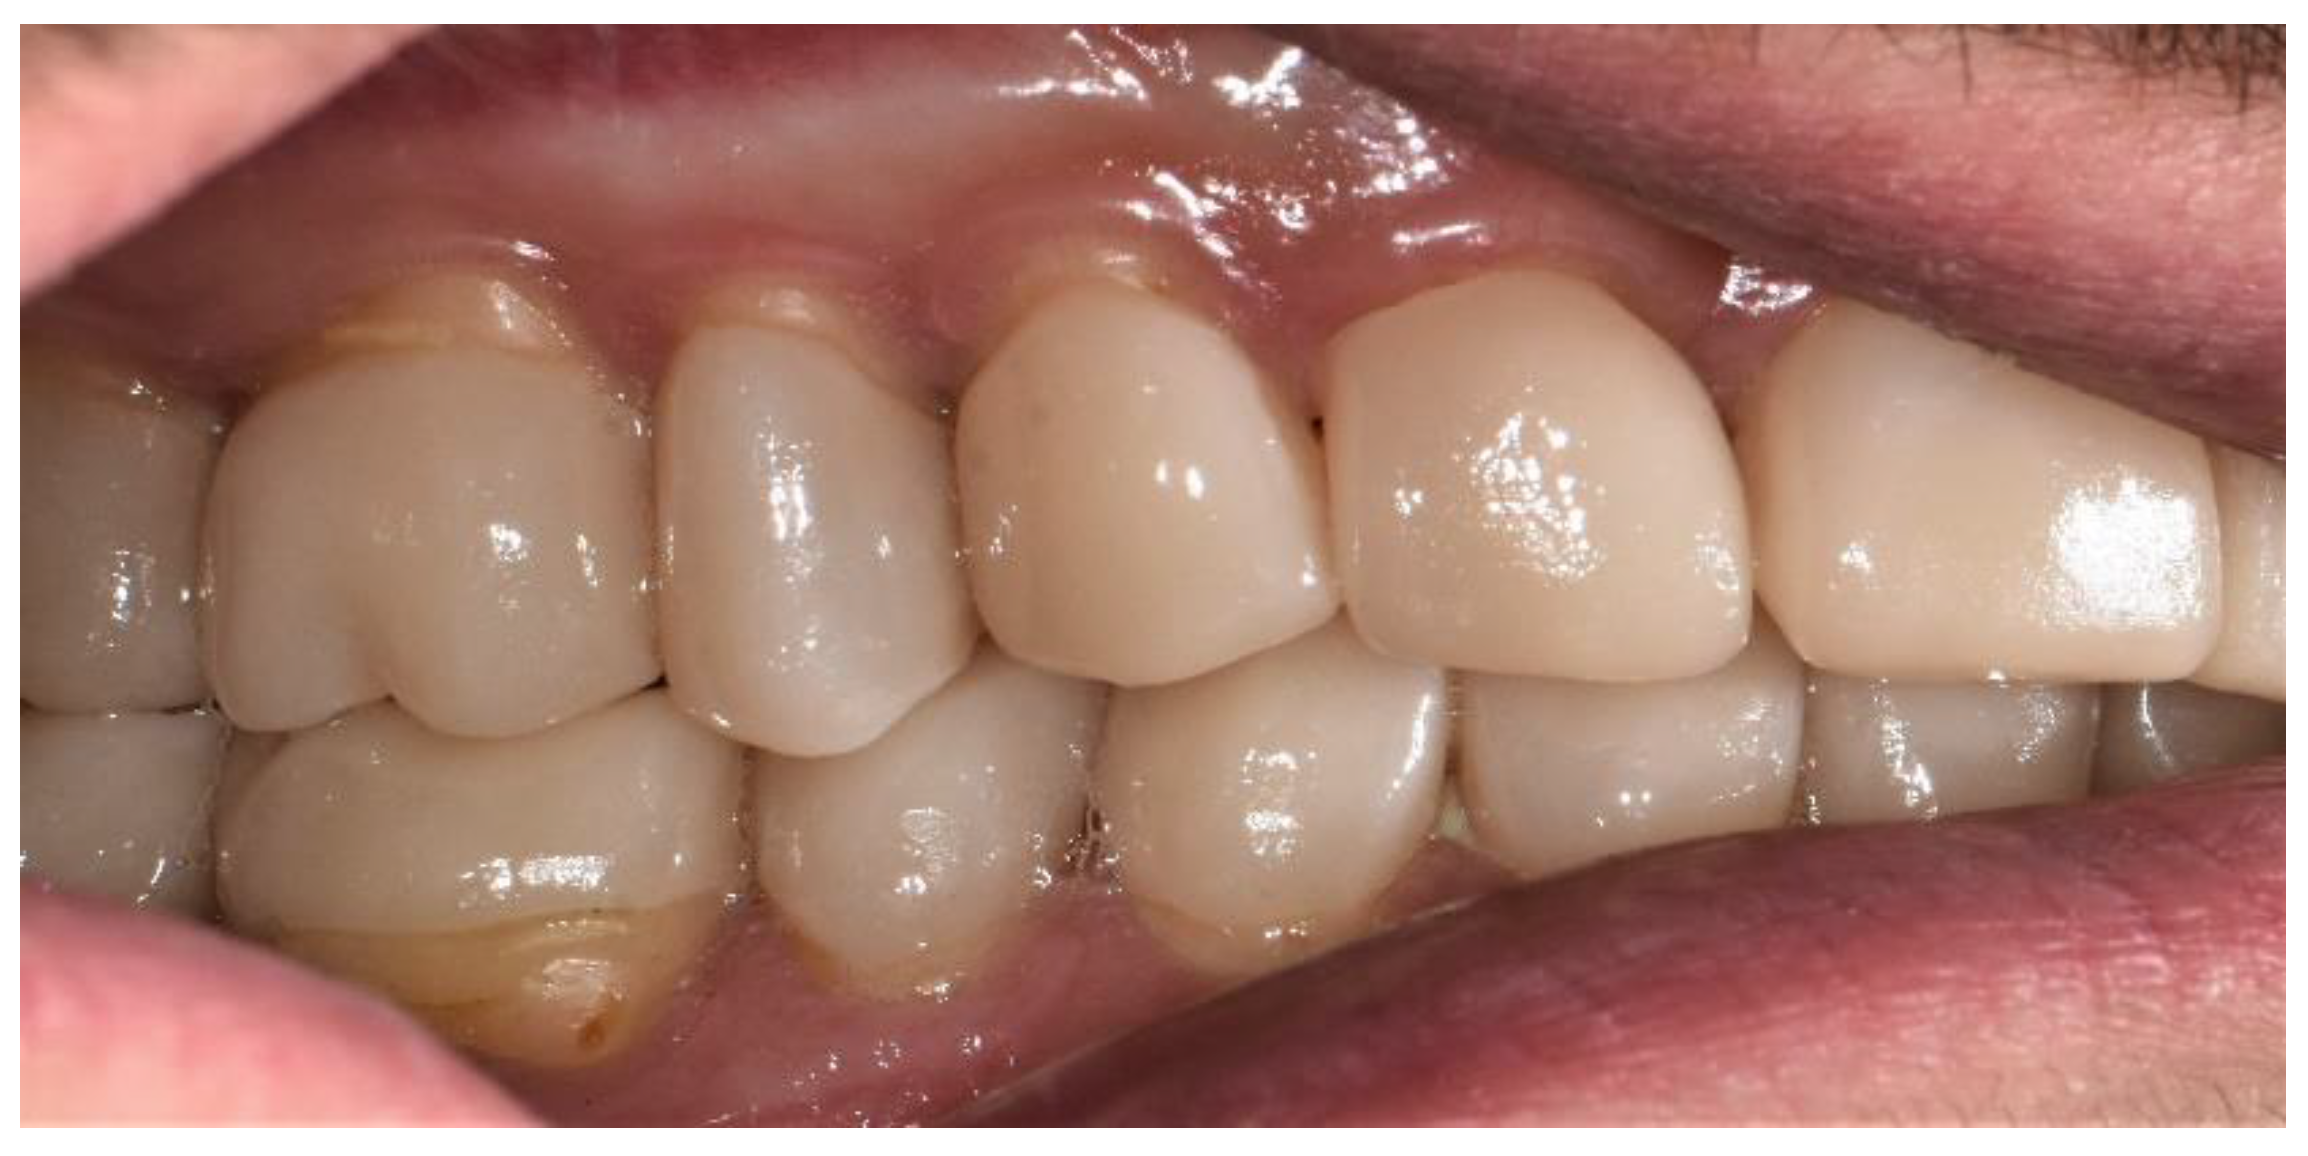

The final view of the upper and lower right side is shown in Figure 14.

Figure 14.

Final view of the right side.